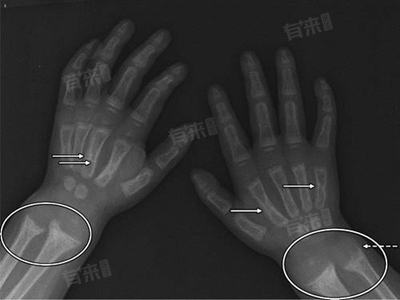

4、骨折风险增加:骨质疏松会使骨骼变得脆弱,骨折的风险显著增加。儿童在日常活动中,即使是轻微的碰撞或摔倒,也可能导致骨折。常见的骨折部位包括手腕、前臂、足踝等。骨折后,孩子会出现局部肿胀、疼痛、活动受限等症状,严重时可能需要手术治疗。

儿童骨质疏松的症状多样且容易被忽视,家长和医生要提高对儿童骨质疏松的认识。如果发现孩子出现上述症状,应及时带孩子到医院进行相关检查,如骨密度检测、X线检查等,以便早期诊断和治疗。